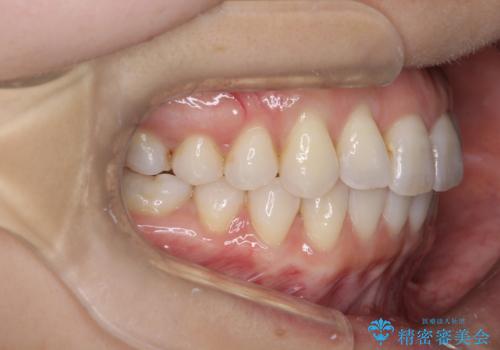

セラミックで歯並びを整えることには限界があります。

また健康な歯を削る必要もあります。

矯正治療は治療期間がかかってしまいますが、不必要に歯を削ることなく、かみ合わせまで考慮して治療が可能です。